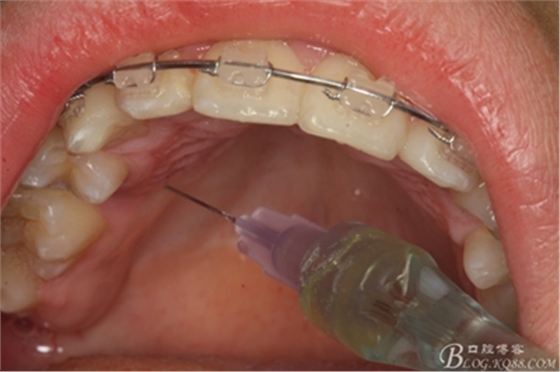

圖5.涂布表面麻醉劑

圖6.唇側(cè)局部無痛浸潤麻醉

圖7.腭側(cè)無痛浸潤麻醉